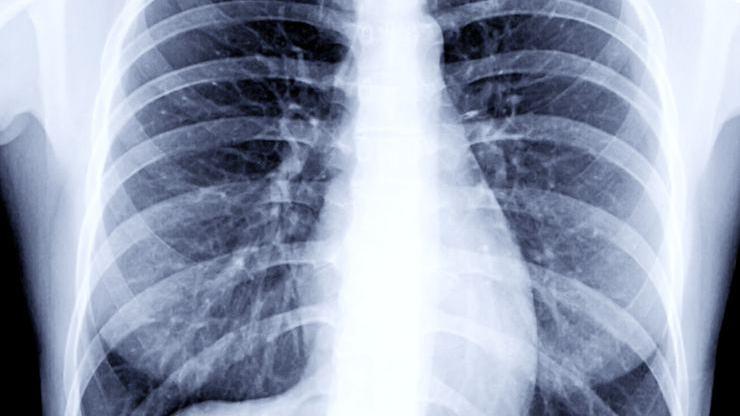

Bazı hastalarda ise haftalarca bulantı, karın ağrısı gibi şikayetler devam edebilir. Hastalığı ağır geçirenlerin ortalama yarısında halsizlik, güçsüzlük, çabuk yorulma şikayetleri haftalar bazen aylarca sürer. Akciğerlerde kalan sekele bağlı yine hafif-orta geçirmiş hastaların 1/3’ünde akciğerde fibrozis dediğimiz elastikiyet kaybı ve kanın oksijenlenmesindeki bozulmaya bağlı olarak nefes darlığı aylarca sürüyor. Hastalığı daha şiddetli geçirenlerde bu tablo daha da ağır olur. İyileşen hastaların yüzde 2.5 oranında taburculuktan 1 ay sonra damar içi pıhtılaşma sorunları geliştiği bildirildi” dedi